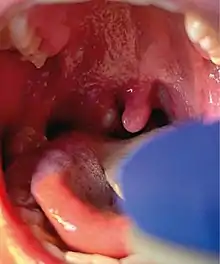

The rash comprises many small lesions which may appear on the palms and soles, face, mouth and throat, genitals or anus.[1] They begin as small flat spots, before becoming small bumps which then fill with fluid and subsequently burst and scab over, persisting for around ten days.[2]